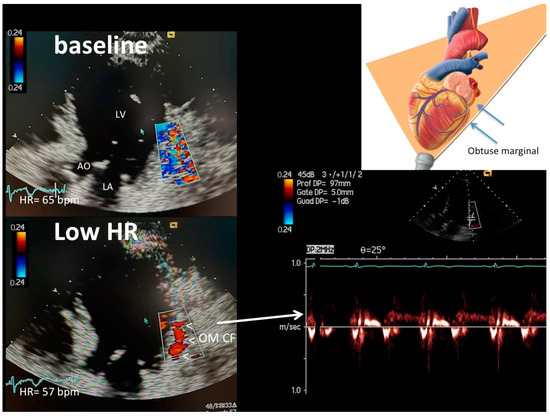

Heart Rate Lowering Significantly Increases Feasibility in Doppler Recording Blood Flow Velocity in Coronaries during Transthoracic Doppler Echocardiography

Background: Coronary blood flow Doppler recording by Transthoracic Doppler in convergent mode (E-Doppler TTE) might be further improved by lowering heart rate (HRL) down to <60 bpm, since low HR < 60 b/m causes a disproportional lengthening of the diastole, so the coronaries are still for a longer time, very much improving the Doppler signal/noise ratio. Methods: A group of 26 patients underwent E-Doppler TTE before and after HR lowering in four branches of the coronary tree, namely, the left main (LMCA); left anterior descending (LAD), subdivided into three segments: proximal, mid and distal; proximal left circumflex (LCx); and obtuse marginal (OM). Color and PW coronary Doppler signal was judged by two expert observers as undetectable (SCORE 1), weak or with clutter artifacts (SCORE 2), or well delineated (SCORE 3). In addition, local accelerated stenotic flow (AsF) was measured in the LAD before and after HRL. Results: Beta-blockers significantly decreased the mean HR from 76 ± 5 to 57 ± 6 bpm (p < 0.001). Before HRL, the Doppler quality was very poor in the proximal and mid-LAD segments (median score value = 1 in both), while in the distal LAD, it was significantly better but still suboptimal (median score value = 1.5, p = 0.009 vs. proximal and mid-LAD score). After HRL, blood flow Doppler recording in the three LAD segments was strikingly improved (median score value = 3, 3 and 3, p = ns), so the effect of HRL was more efficacious in the two more proximal LAD segments. In 10 patients undergoing coronary angiography (CA), no AsF as expression of transtenotic velocity was detected at baseline. After HRL, thanks to the better quality and length of color flow, ASF was detected in five patients while in five others, it was not in perfect agreement with CA (Spearman correlation coefficient = 1, p < 0.01). The color flow in the proximal LCx and OM was extremely poor at baseline (color flow length 0 and 0, median (interquartile range) mm, respectively) and improved considerably after HRL (color flow length 23 [13.5] and 25 [12.0] mm, respectively, p < 0.001). Conclusions: HRL greatly improved the success rate of blood flow Doppler recording in coronaries, not only in the LAD, but also in the LCx. Therefore, AsF for stenosis detection and coronary flow reserve assessment can have wider clinical applications. However, further studies with larger samples are needed to confirm these results. Full article